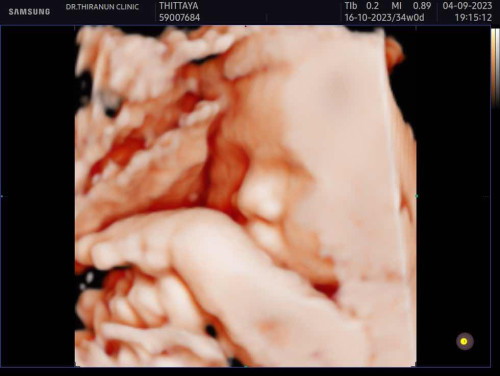

เด็ก34วีคคคค

ซาวน์ล่าสุด34วีค หนัก2071gเองค่ะ แต่ป้าหมอบอกหนูหนักตามเกณฑ์นะคะ🥰